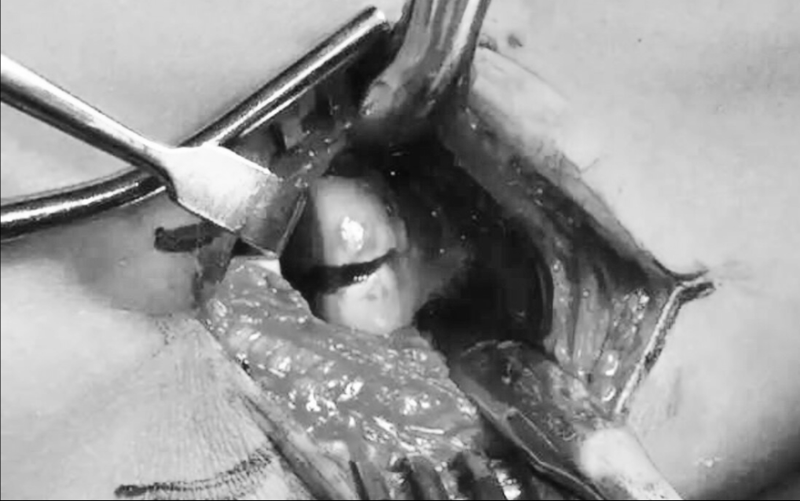

图8 EDC入路切口

图9 骨折固定